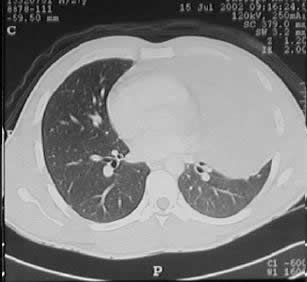

un paciente joven, con un gran tumor del mediastino anterosuperior de rápido

crecimiento, correlacionando su tamaño entre la radiografía

del tórax y los hallazgos tomográficos realizado 15 días

después, y las condiciones físicas al momento de su intervención,

con gran dificultad respiratoria.

Las características

macroscópicas y los hallazgos a la toracotomía mostraron

un tumor sólido bien limitado, de aspecto muy fibrótico,

con verdaderos planos de clivaje para su disección, sin adenopatias

satelites, ni invasión de estructuras vitales, que a pesar de su